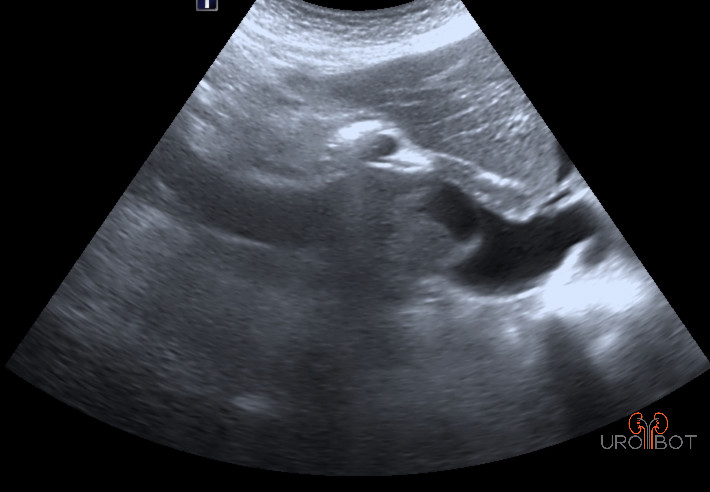

In der Früherkennung ist der Ultraschall die führende Untersuchung. Ab einer Größe von 2 cm kann man bereits bösartige Tumore von gutartigen Zysten unterscheiden. Doch obwohl die Qualität der heutigen Ultraschallgeräte stark zugenommen hat, wird man zu weiteren Unterscheidung und Klassifizierung radiologische Verfahren wie die CT (Computertomographie) oder aber die MRT (Magnetresonanztomographie) einsetzen.

Das Video zeigt eine sonographische Untersuchung der rechen Seite mit Nachweis eines großen Tumorthrombus in der unteren Hohlvene.